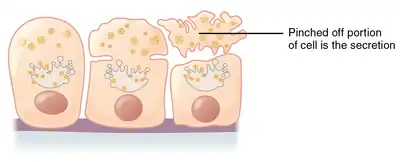

Apocrine secretion

Apocrine gland

Apocrine (/ˈæpəkrɪn/)[1] is a term used to classify the mode of secretion of exocrine glands. In apocrine secretion, secretory cells accumulate material at their apical ends, and this material then buds off from the cells, forming extracellular vesicles. The secretory cells therefore lose part of their cytoplasm in the process of secretion.

Apocrine secretion is less damaging to the gland than holocrine secretion (which destroys a cell) but more damaging than merocrine secretion (exocytosis).